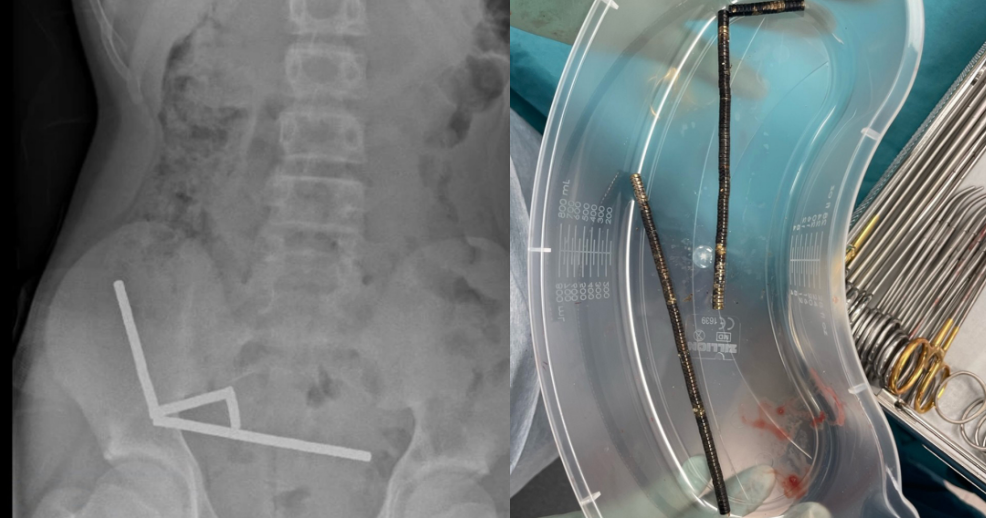

During exploratory surgery, doctors successfully removed the magnet chains. However, the damage was so severe that the boy required the removal of part of his bowel. He spent eight days recovering in the hospital before being discharged.